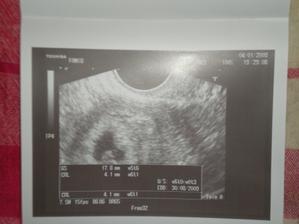

4/1 - od pátku jsem měla vysokou horečku, k tomu silné bolesti v podbřišku, tak mi to nedalo a vydali jsme se na pohotovost do Motola, výsledkem je gravidita intrauterina 5+2, podle gestačního váčku 5+6 a podle velikosti na UTZ 6+1, měříme 4,1mm a hlavně TLUČE NÁM SRDÍČKO... zatím prý je to vidět malinko, ale jsme ještě přeci moc malí 🙂)))